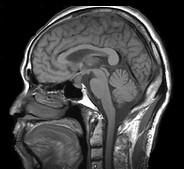

问题 男,头痛7月余,伴左侧面部麻木,疼痛剧烈时伴恶心,无呕吐,请根据所提供图像,选择最可能的诊断()

选项 A.垂体瘤 B.颅咽管瘤 C.生殖细胞瘤 D.脑膜瘤 E.胶质瘤

答案 B